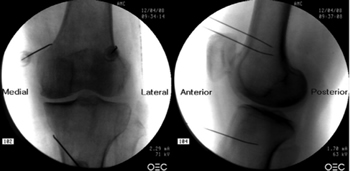

Figure 1

Figure 2

Figure 3

Figure 4

Figure 5